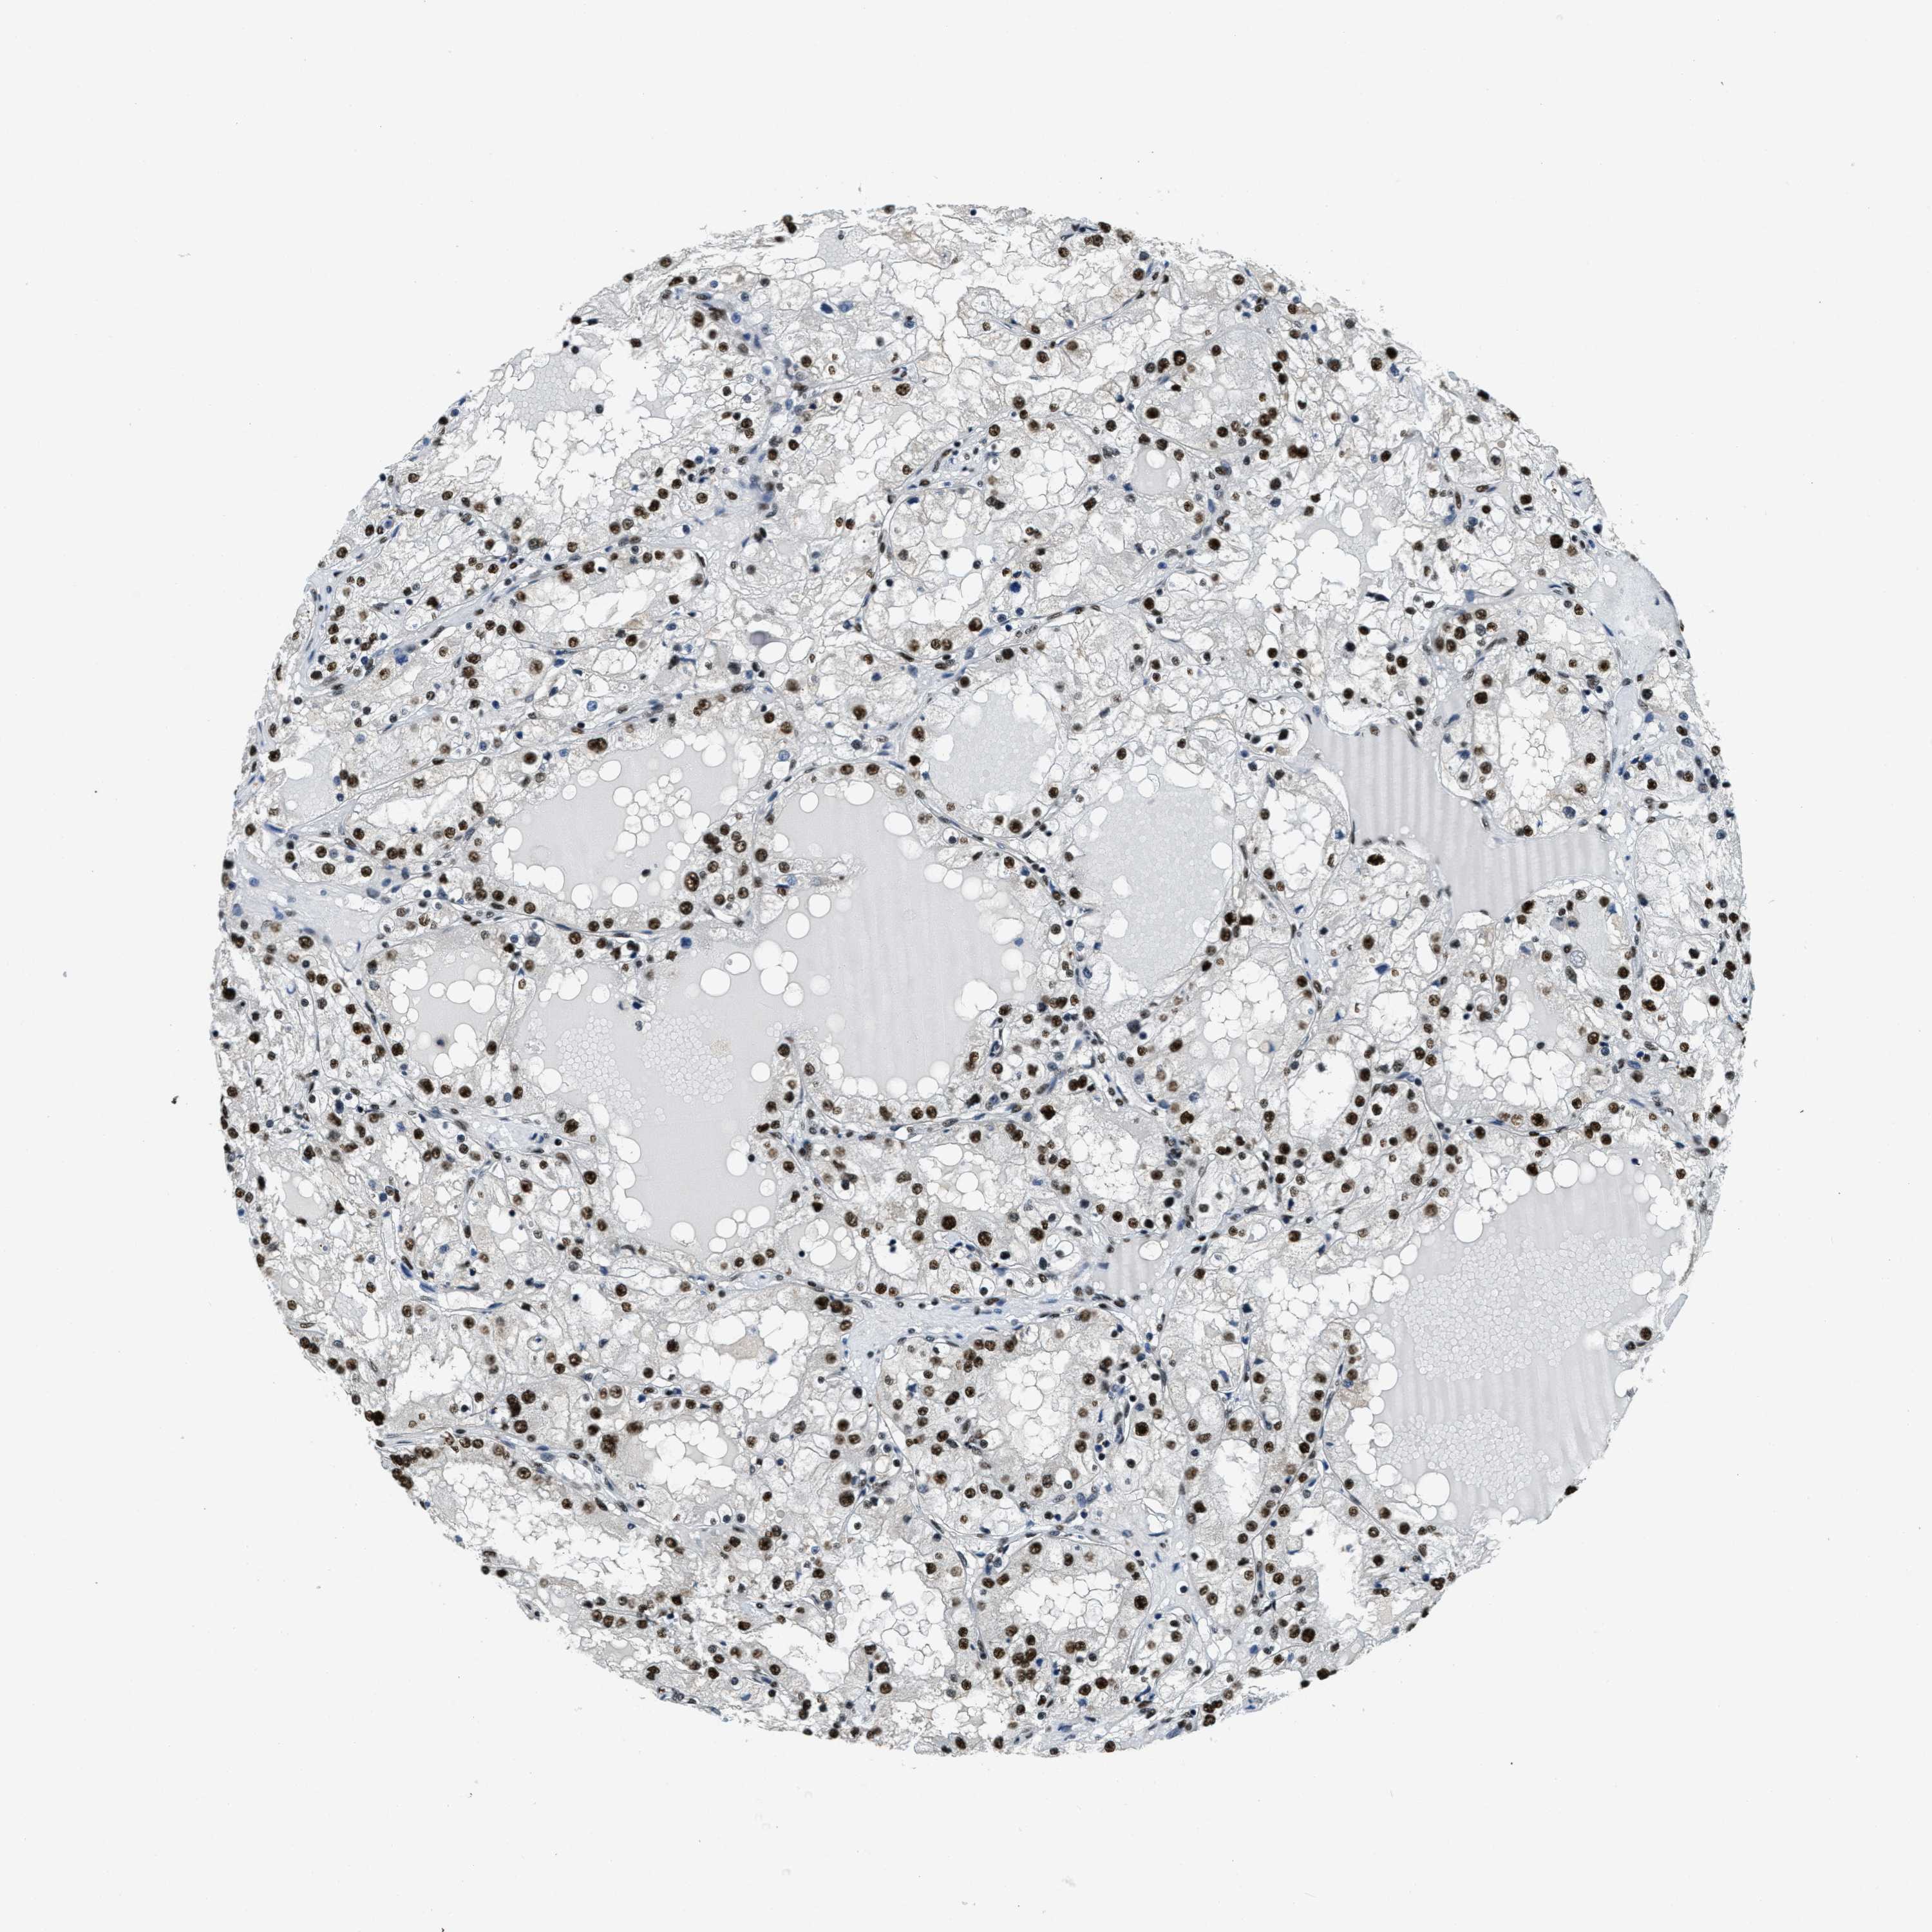

SSB is not prognostic in Kidney Renal Clear Cell Carcinoma (TCGA)